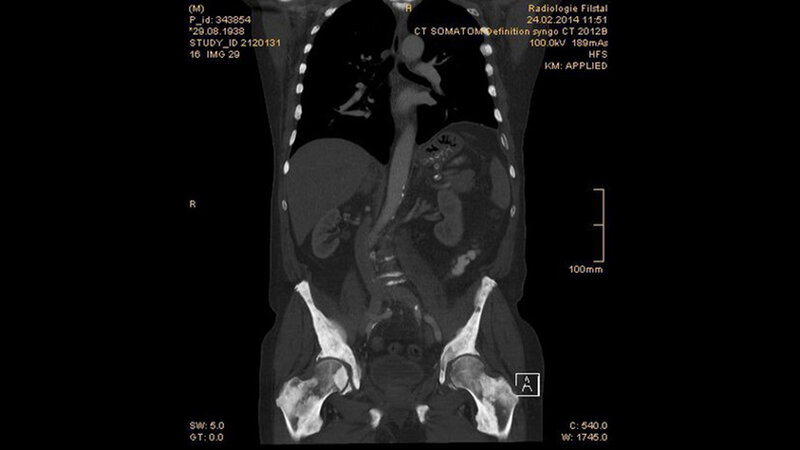

Tumoröse Veränderungen: Osteoplastische Metastasen

Das Prostatakarzinom ist die zweithäufi gste Ursache der krebsbeding-ten Todesfälle bei Männern. Die Metastasen sind hauptsächlich os-teosklerotisch und durch exzessive Osteoblastenaktivität verursacht. Die Diagnose wird durch klinische, biochemische und histologische Untersuchungen gestellt. Die bildgebende Diagnostik hat eine Be-deutung für das Staging.